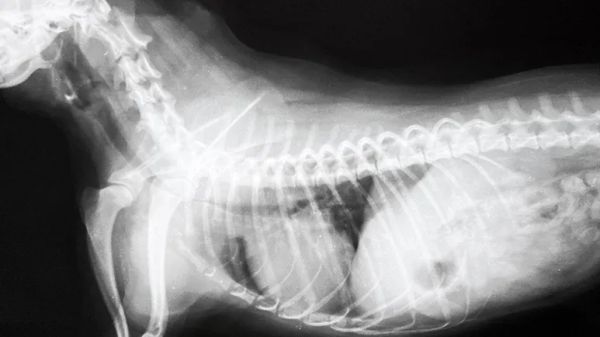

A dog with arthritis may limp, move slowly or have difficulty standing up after lying down. But what about the more subtle signs of degenerative joint disease that can affect dogs of all ages and sizes? When pet parents see these signs, they most likely wouldn't suspect joint disease, but should.